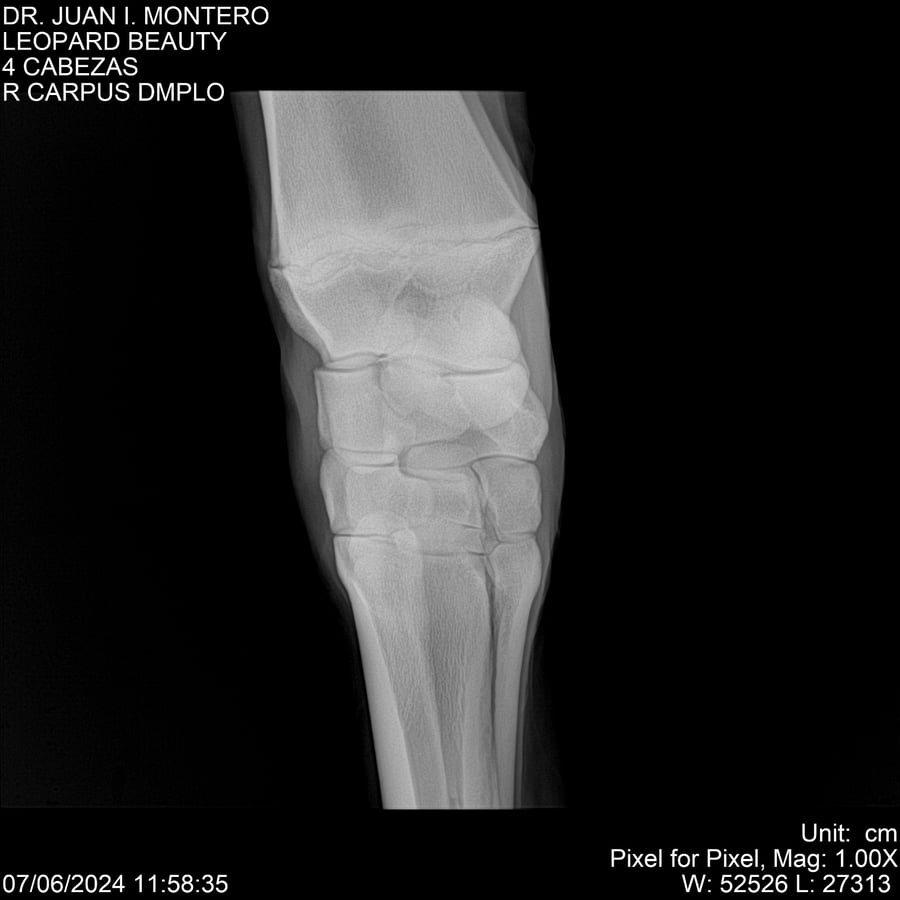

LOTE 16, LEOPARD BEAUTY Lote Anterior Volver al remate Lote Siguiente Ficha Contacto Montevideo - Ficha del Lote Identificador: #281095 Categoría: Yeguarizos Montevideo - 50 Visualizaciones ClicData Contacto Empresa: Abelenda N. R., Walter Hugo Nombre*: Teléfono* : E-mail* : Mensaje Enviar Registrese gratis Este contenido Exclusivo está disponible sólo para usuarios registrados Ingresar